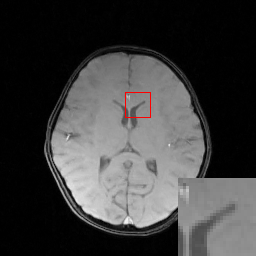

We evaluate the proposed DECN framework using PSNR and SSIM (structural similarity index) [30] as quantitative image quality assessment measures. We give the quantitative reconstruction results of all the test data on different under-sampling patterns and different under-sampling ratios in Table II. We show the Cartesian 30%percent3030\% under-sampling mask in Figure 6(b) and the Random 20%percent2020\% under-sampling mask in Figure 7(b). We observe that DECN improved all off-the-shelf CS-MRI inversion methods on all the under-sampling patterns. Since the Random mask enjoys the more incoherence than the Cartesian mask with the same under-sampling ratio, the CS-MRI achieves better reconstruction quality on the Random masks. Also, we observe the plain DC-CNN model already achieves good reconstruction accuracy, leaving less structural errors for the error correction module, leading to the limited performance improvement about 0.1 dB on the Random 20%percent2020\% and 30%percent3030\% masks. While for other CS-MRI inversions on various sampling patterns, the improvements are at least 1.5dB or even up to 3.5 dB.

In Figure 6, we show reconstruction results and the corresponding error images of an example from the test data on the 1D 30%percent3030\% under-sampling mask. With local magnification on the red box, we observe that by learning the error correction module, the fine details, especially the low-contrast structures are better preserved, leading to a better reconstruction.

Refer to caption

(a) Fully-sampled

(b) 1D 30%percent3030\% Mask

(c) Zero-filled

(d) Full-sampled

(e) Full-sampled

(f) Full-sampled

(g) Full-sampled

(h) TLMRI

(i) PANO

(j) GBRWT

(k) DC-CNN

(l) TLMRI-DECN

(m) PANO-DECN

(n) GBRWT-DECN

(o) DC-CNN-DECN

(p) ΔΔ\Delta TLMRI

(q) ΔΔ\Delta PANO

(r) ΔΔ\Delta GBRWT

(s) ΔΔ\Delta DC-CNN

(t) ΔΔ\Delta TLMRI-DECN

(u) ΔΔ\Delta PANO-DECN

(v) ΔΔ\Delta GBRWT-DECN

(w) ΔΔ\Delta DC-CNN-DECN

Figure 6: We show the reconstruction results of our DECN model with local area magnification. We also show the reconstruction error for our DECN model under different guide module in the last row.